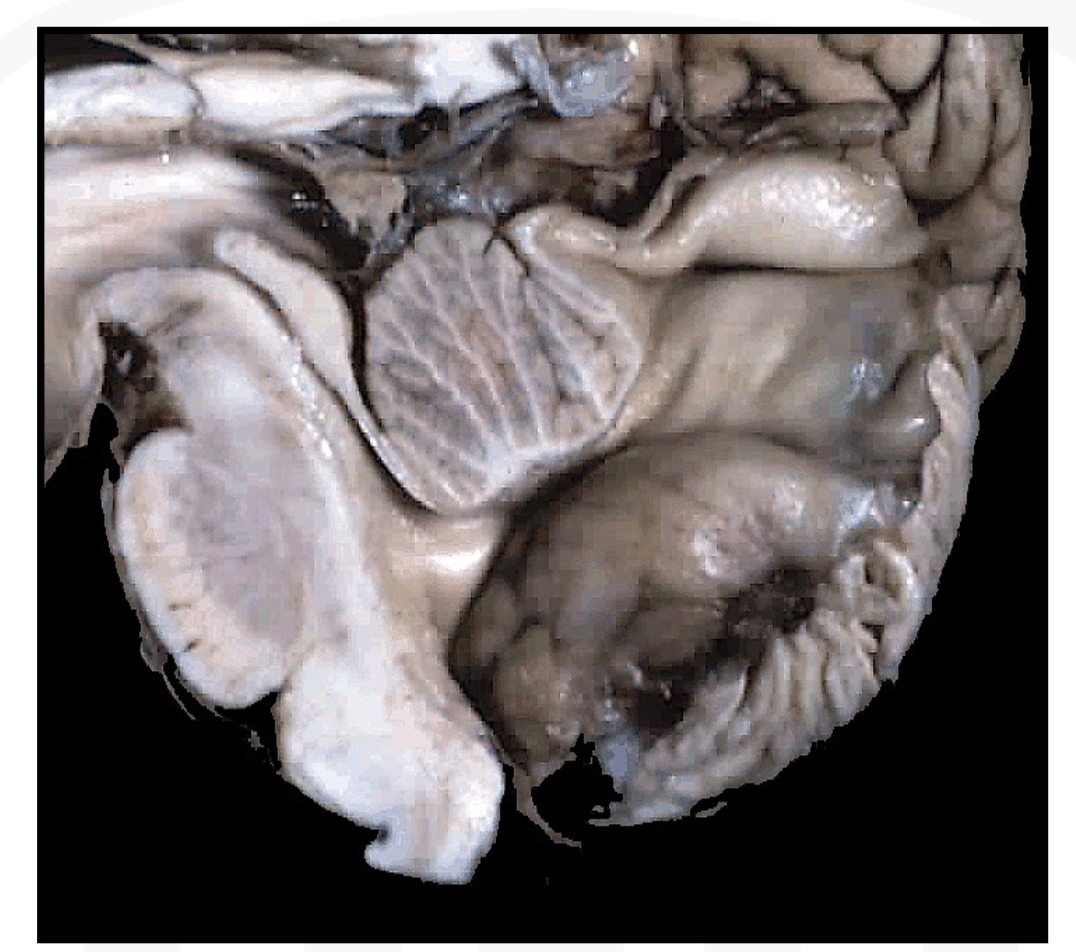

Describe this

Dandy–Walker malformation. Note the very hypoplastic inferior cerebellar vermis and the cystic dilatation of the fourth ventricle.